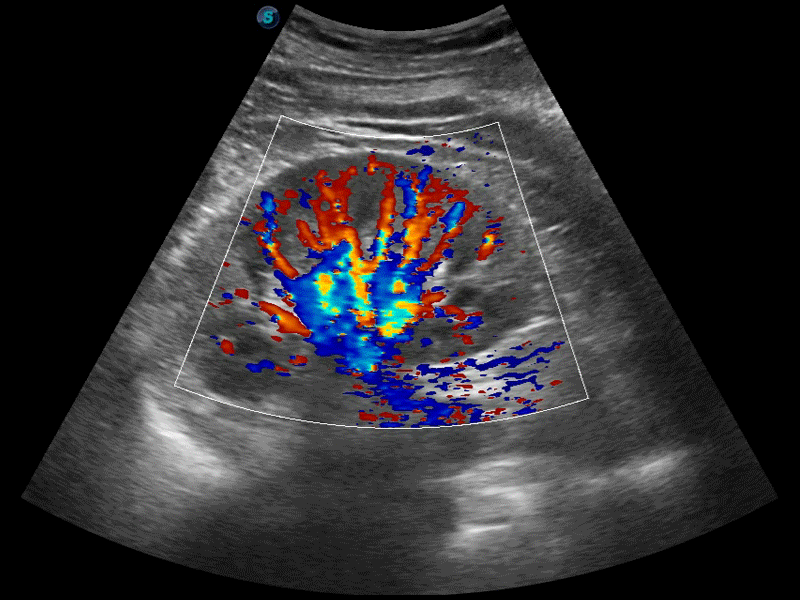

彩色多普勒超声诊断系统

高分辨率血流成像技术提高了对低速血流信号的检测能力。在提高空间分辨率的同时,也克服了血流外溢现象,为用户提供更加真实的血流动力学信息。